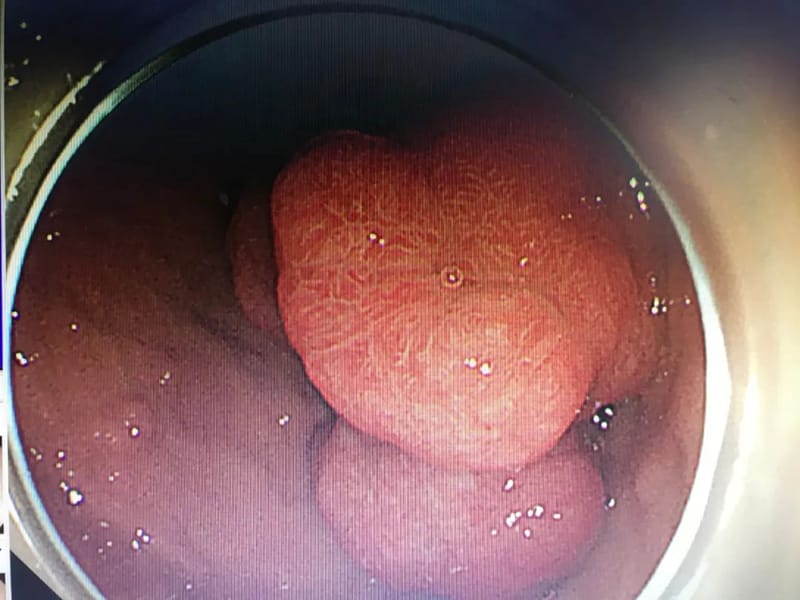

13岁患儿薛某某,是一名黑斑息肉综合征的患者,有结肠癌家族史,因消化道出血入院,在完善胃肠镜检查发现其以胃内为主有几十枚息肉样病变,其中最大者达到6*6.5cm,为了让患儿能得到最合理、最优化、最小创伤的治疗,郭军主任团队进行了多次术前讨论。最终确定胃镜、肠镜下经内镜息肉切除,但行内镜切除的话,手术难度大,风险高。在充分术前准备后,郭军主任经过3小时的内镜下手术,患儿病灶被完整切除,现恢复良好,进入密切随访阶段。